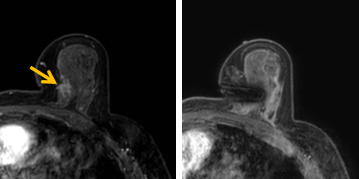

患者李女士磁共振檢查發(fā)現右乳內側高度可疑病變,病變小摸不到,超聲和X線攝影(鉬靶)都看不到,怎么辦?要想明確病變性質,必須進行磁共振引導下精準足量的活檢,但是這種技術操作難度大、軟硬件要求高。

經過仔細查體并分析所有影像資料,陳寶瑩發(fā)現,病變靠近胸大肌,容易造成術中損傷。患者乳房較小,病變在內側,導致乳房不易固定,進針難度大,與患者充分溝通后,陳寶瑩帶領團隊,制定了細致的操作方案,術中,醫(yī)護團隊反復調整體位和固定架的角度及方向,利用隔離技術保護好周圍組織。受乳房形態(tài)和病變位置的限制,醫(yī)生只能蹲著、跪著進行操作,經過30多分鐘終于順利完成,精準獲取了足量的組織,而且一針到位,創(chuàng)傷小、出血少,患者沒有任何不適,做完即回家休息。幾天后,病理證實是一種特殊類型的早期乳腺癌,為后續(xù)進一步治療方案的制訂提供了準確依據。

陳寶瑩教授介紹,乳腺磁共振微創(chuàng)診療技術是針對磁共振發(fā)現的可疑病變,進行磁共振引導的導絲定位、旋切活檢、靶釘植入及消融治療的微創(chuàng)診療技術。磁共振特有的多模態(tài)和功能成像,不但能顯示出更多其他檢查發(fā)現不了的可疑病變,而且能顯示出病變準確的范圍和活性區(qū)域,因此MR引導的乳腺病變真空輔助旋切技術相較于其他常規(guī)活檢技術,具有更精準、活性成分取材充足的特點,明顯降低了病理的假陰性率,提高了準確性。